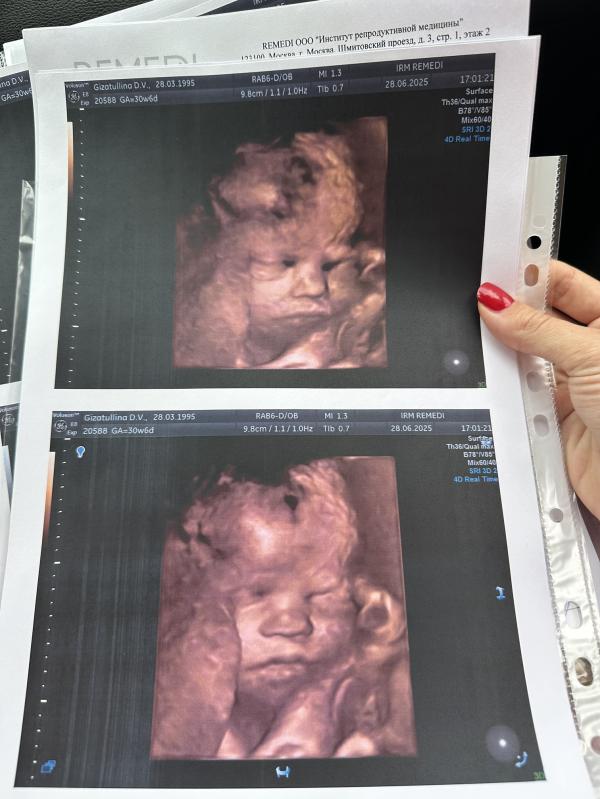

Сегодня ровно 31 неделя, отметили походом на узи семейством 🤗

Первый раз делала 3д, с дочкой 10 лет назад не знала про такое.

А сейчас ляля уже такая большая🥹прям новорожденный человечек❤️даже шевелюра говорит у неё уже есть 😍

Всё соответствует сроку, кровотоки, плацента, органы, всё хорошо слава Богу🫶🏻🙏🏻

В ровно 31 недель весит 1680гр., длина 41см. Шейка моя 43мм.

Но сидит на попке, как я и предполагала всё это время 🤭Врач сказала пока ей так удобнее, наверное через Недельки три перевернется )🙏🏻

Делюсь с вами нашей бусинкой ☺️ счастлива!желаю испытать эти эмоции тем, кто давно этого желает !🫶🏻

P.S. теперь сижу и Сравниваю: похожи ли с Алиской 🤭предпоследнее фото Алиска, последнее фото ляля сегодня ))